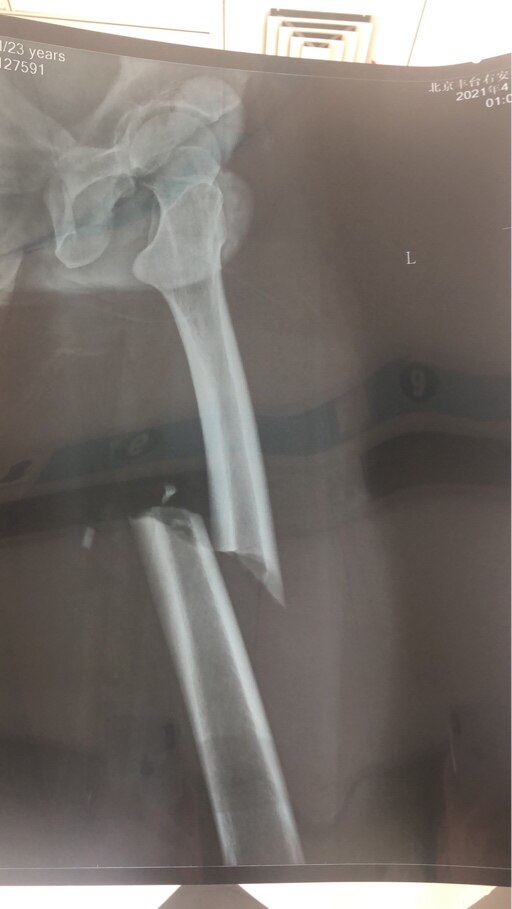

兄弟你这个现在怎么样了,几个月了。现在是一个什么状况。因为我也和你差不多